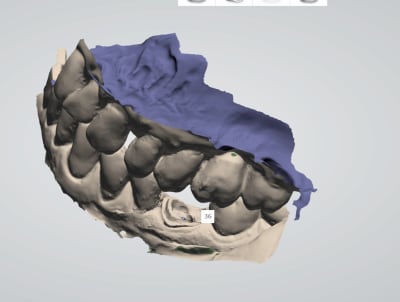

chicot29

26/02/2018 à 21h45

Une autre.

T'en as rien a branler de la couleur. le protho travaille sur le platre.

Putain si même chicot29 a une cam, va faloir que je m'y mette.

Franchement ça donne pas envie, on voit pas bien du tout les limites.

Tu n’arrives pas à voir les limites ici ?!?